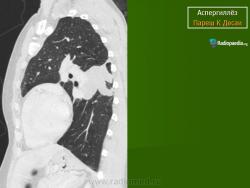

Аспергиллёз.

Продолжение.